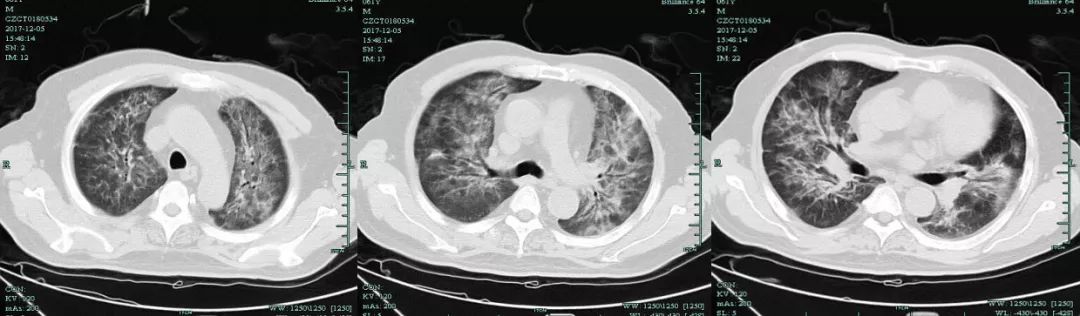

12.5复查肺部CT提示病灶较前明显进展。

【图2】12月5日肺部CT复查提示两肺弥漫渗出影伴肺间隔增厚,较11.30明显进展